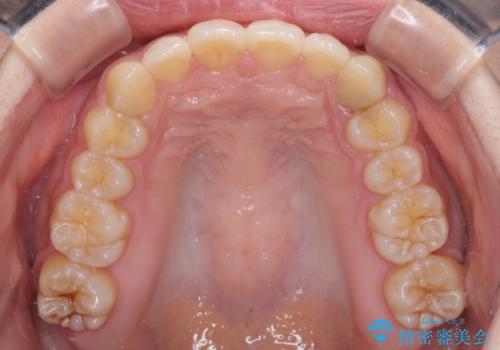

奥歯の倒れた歯を改善 インビザラインでの矯正治療

- 前歯のデコボコと奥歯の不正咬合を気にして来院された患者様です。

左右の大臼歯が全て鋏状咬合(シザーズバイト)になっており、治療が難航することが予想されましたが、インビザラインにより治療を行うこととしました。

最難関と思われたシザーズバイトは比較的短期間で解消されました。

しかし、治療中に2度の出産を経験され、治療期間は長くなってしまいましたが、咬みやすく、清掃しやすい歯列を獲得することができました。